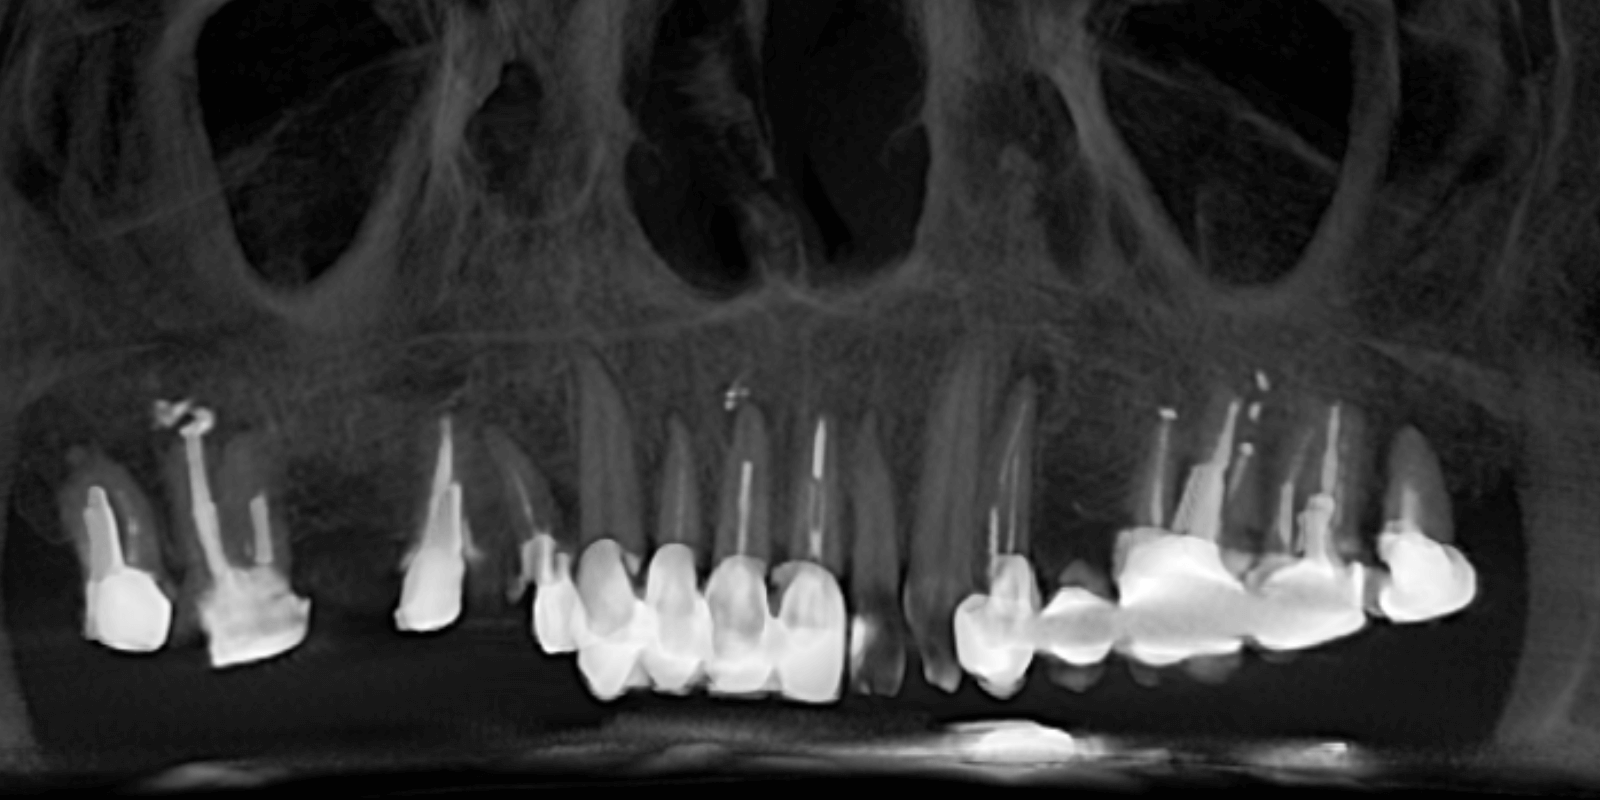

Фронтальный участок зубов выполнить керамическими ортопедическими конструкциями. Это был сложный случай, но абсолютно реальный для нашей команды. Мы составили индивидуальный план лечения, разделили его на этапы, учли временные возможности пациентки (которая жила не в Киеве) и выбрали протокол, позволявший максимально сохранить и восстановить.

Да, это был сложный путь. И долгий — почти год. Но результат того стоил.

Итог лечения

Один год. Четыре визита. Долгие паузы между этапами. Много логистики, много моментов сомнения. Но в конце — женщина, которая не просто получила новые зубы. Она вернула себе спокойствие, уверенность и легкость — улыбка стала не “подарком стоматологов”, а ее личной победой.

Это был сложный, но очень теплый процесс сотрудничества. Мы благодарны за доверие и рады видеть результат, который меняет жизнь. Никакой боли. Надежные импланты. Красивая, естественная улыбка. И самое главное — уверенность, которую видно в глазах пациентки.